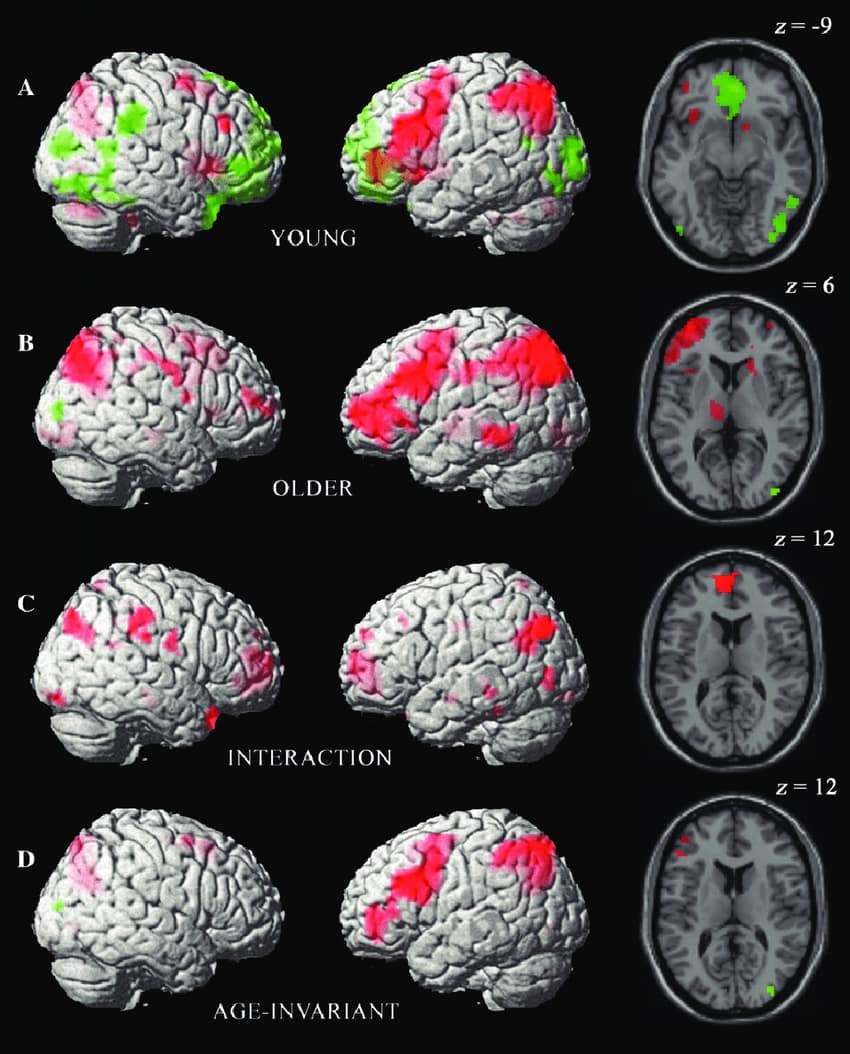

Mozak – ne opada, već se menja

Brzina obrade opada, ali:

- znanje raste

- iskustvo raste

- emocionalna stabilnost raste

👉 To znači:

mladi = brzina

stariji = mudrost